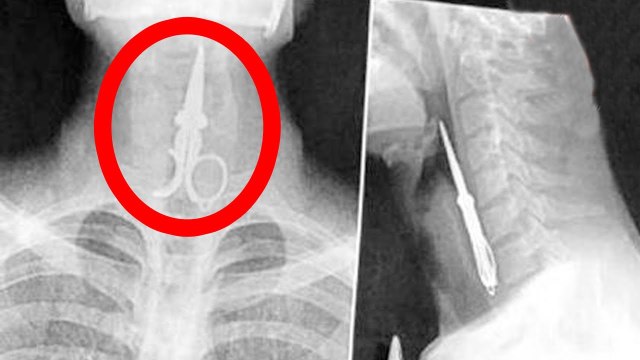

O voo 8243 da Azerbaijan Airlines foi abatido a 25 de dezembro por um míssil de um sistema russo Pantsir-S1, causando 38 mortos e 29 feridos, como noticiou a Euronews em dezembro e janeiro.